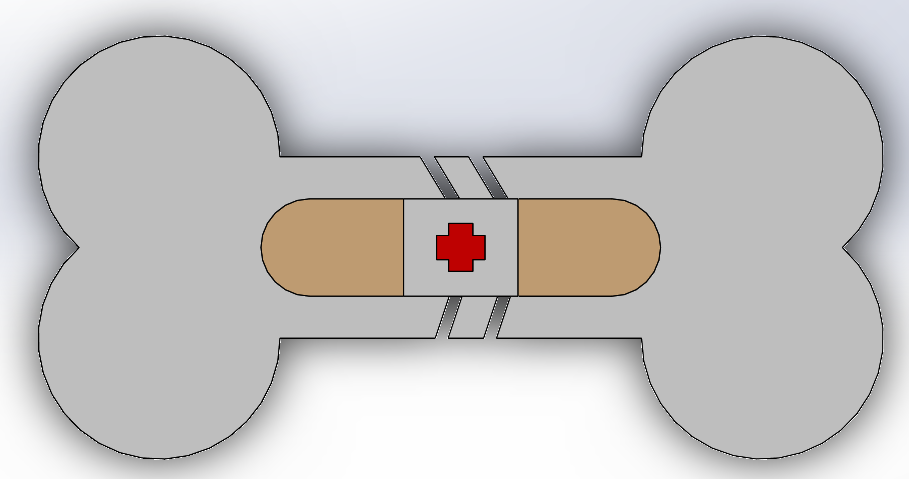

Problem

Plates and screws are used to realign broken bones and allow them to heal properly. During this process, it is possible for the screws to experience failure.

Screw Failure Mechanism

Varying loads and recurrent movements lead to the loosening of screws. Without proper fixation, the bone will not heal properly.

Current Strategy

Reducing relative movement between the bone and the plate will reduce the loosening of the screws. Adding a texture on the plate will increase the frictional force between the bone and plate and prevent failure.